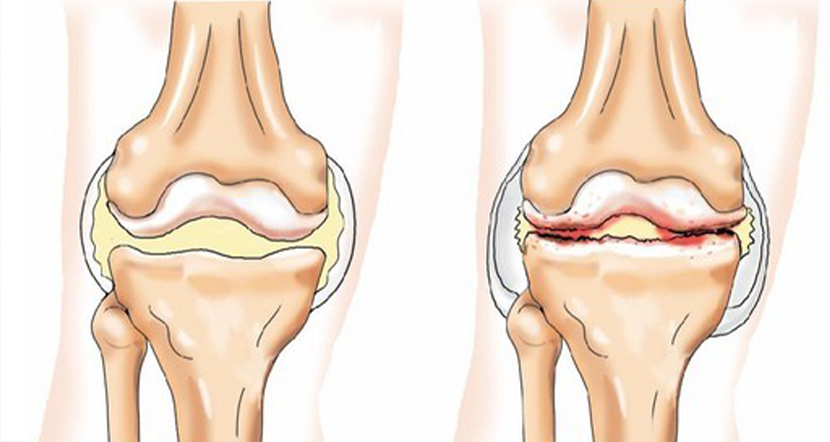

Хвороба, пов'язана з дегенеративними змінами (зношенням) хрящової тканини, яка покриває суглобні поверхні кісток і забезпечує вільні рухи кінцівок.

Якщо вже виявлені виражені дефекти хрящової тканини – консервативна терапія безсильна і для лікування артрозу колінного суглоба необхідна операція. У окремих випадках цикл розвитку патології від перших ознак до тяжкої інвалідності може зайняти всього декілька років.

При гонартрозі операція артроскопії здатна радикально позбавити пацієнта від болю в колі та відновити функцію ураженої кінцівки. Справа в тому, що вже при першій-другій стадіях захворювання на медіальному (внутрішньому) меніску виникають грубі зміни внутрішньосудинної тканини.

Консервативні методи безсильні для усунення органічного ураження цієї, розташованої усередині коліна, своєрідної фізіологічної «прокладки». В результаті не лише прогресує біль в колі, але й створюються всі умови для швидкого його руйнування. Проте, малоінвазивна операція на меніску за допомогою артроскопії дозволить добитися тривалої та стійкої ремісії захворювання.